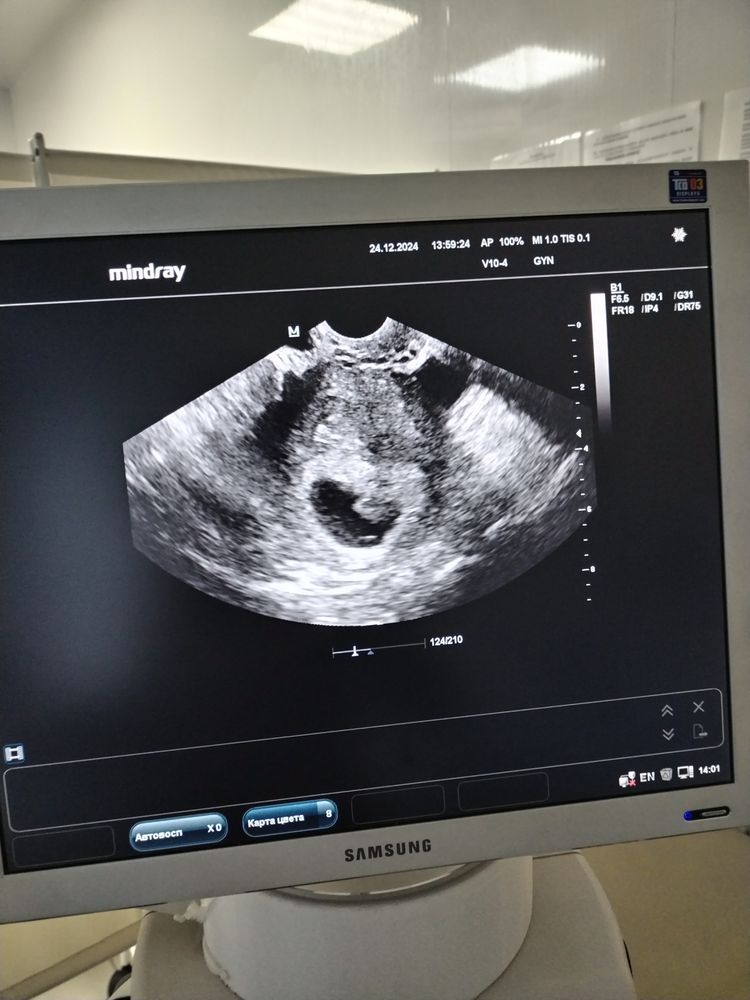

23 дпп узи